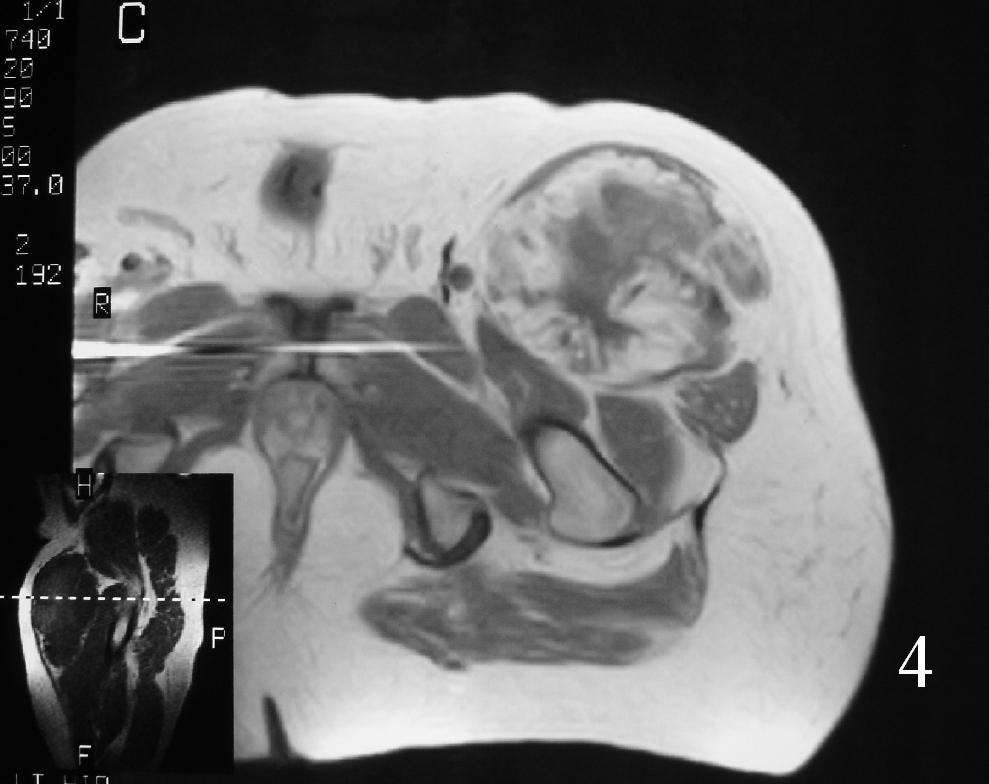

MRI (Fig. 3-7)

• Shows lobulated soft tissue mass

• Signal intensity similar to that of skeletal muscle on T1W

• Heterogenous signal intensity greater than that of fat on T2W

Fig. 3

Fig. 4

Fig. 5

Fig. 6

Fig. 7

Fig. 3-7 Axial MRI of the lower extremity shows an extraskeletal soft tissue chondrosarcoma in different sequences with and without contrast (Fig. 3, 4, 5). Sagittal MRI (Fig. 6, 7) T1 with-without contrast demonstrates enhancement of the mass